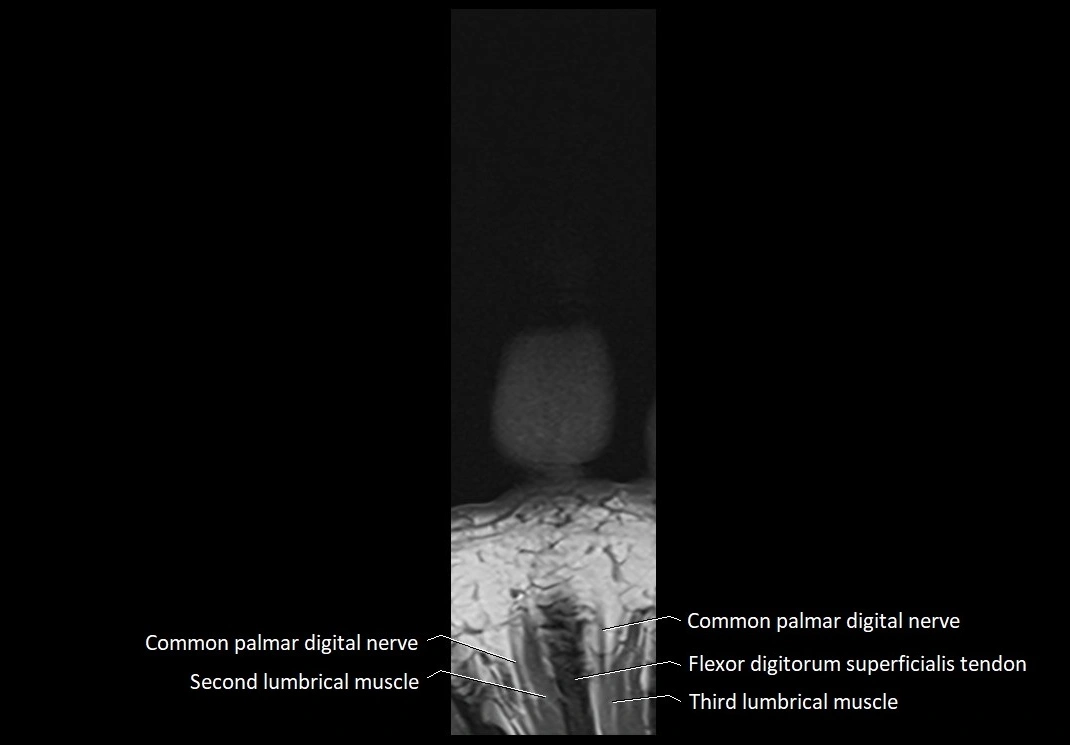

MRI images

image